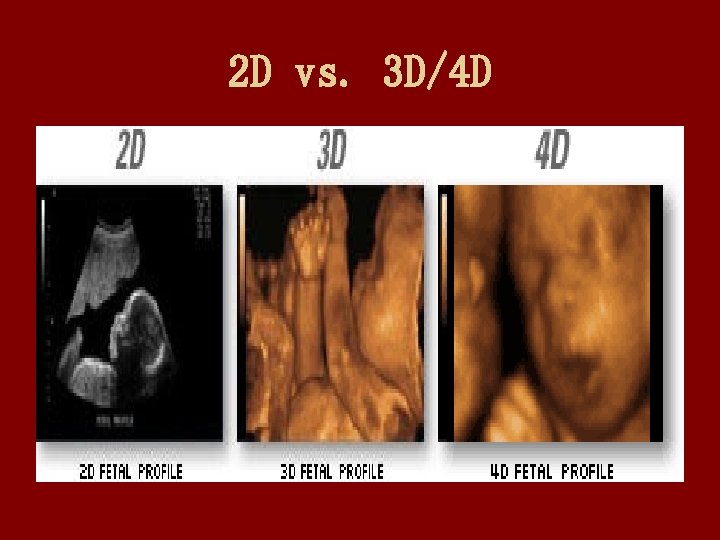

2 D vs. 3 D/4 D